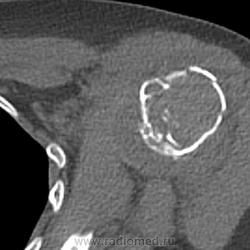

или гигантоклеточная опухоль. Требуется морфологическая верификация

Интересно, что структура разная, кость не вздута, кортикал истончен, но сохранен. Болей до травмы совершенно не было. Думаю, травматологи прооперируют, надеюсь узнать результаты гистологии - сообщу. Спасибо. Татьяна Валентиновна. Я сначала на аневризмальную кисту подумала, но не уверена была.

При ГКО бывает вторичная аневризмальная киста